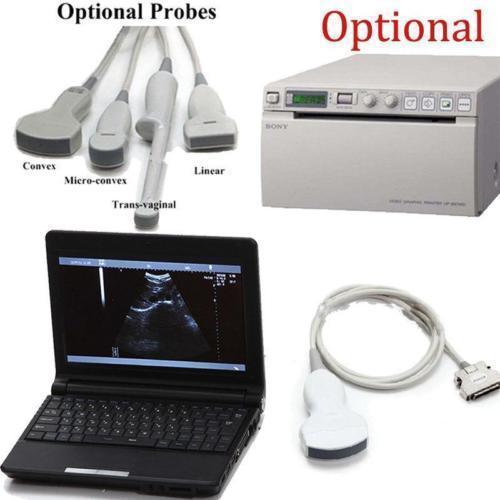

Laptop Ultrasound Machine Portable Medical Scanner with Transvaginal Probe USA 6945040100362